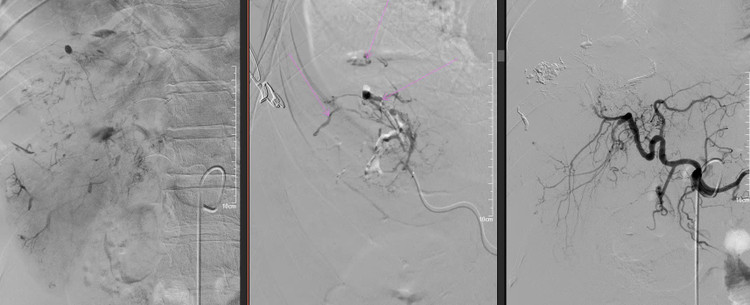

Khối u gan vỡ đã được nút mạch thành công - Ảnh BVCC

Ê-kíp đã thực hiện nút tắc chọn lọc nhánh mạch phân thùy trước bằng hỗn dịch keo sinh học – Lipiodol, giúp cầm máu thành công. Sau can thiệp, huyết động và toàn trạng người bệnh ổn định, được chuyển về khoa Hồi sức cấp cứu để tiếp tục điều trị.